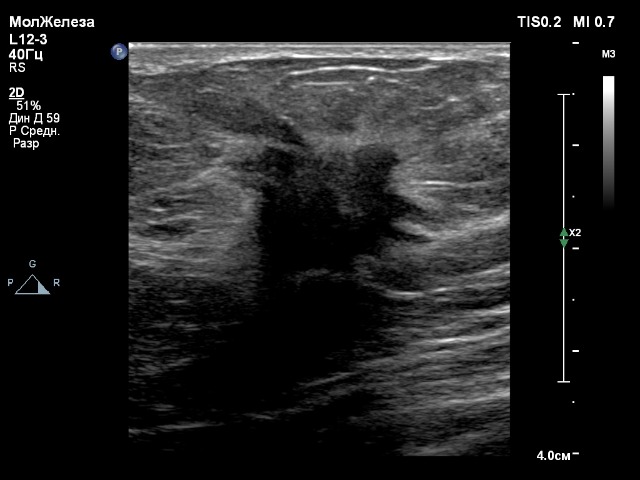

1. Датчик L12-3

Сложно судить, ведь настройки В-режима в каждом скрине разные

Выбирал предустановленные настройки путём нажатия пресета:Сложно судить, ведь настройки В-режима в каждом скрине разные

- вены нижних конечностей для датчиков L12-3 и eL18-4;

- вены для датчика L18-5.

Глубина сканирования одинаковая, 5 см.

Во-первых, датчик L12-3 всё же лучше для сосудов (вены и артерии конечностей, БЦА). Когда сравниваешь на одном пациенте, есть разница. Датчик L12-3 с более ясной картинкой. Если увеличить Gain на датчике eL18-4, пойдут помехи.